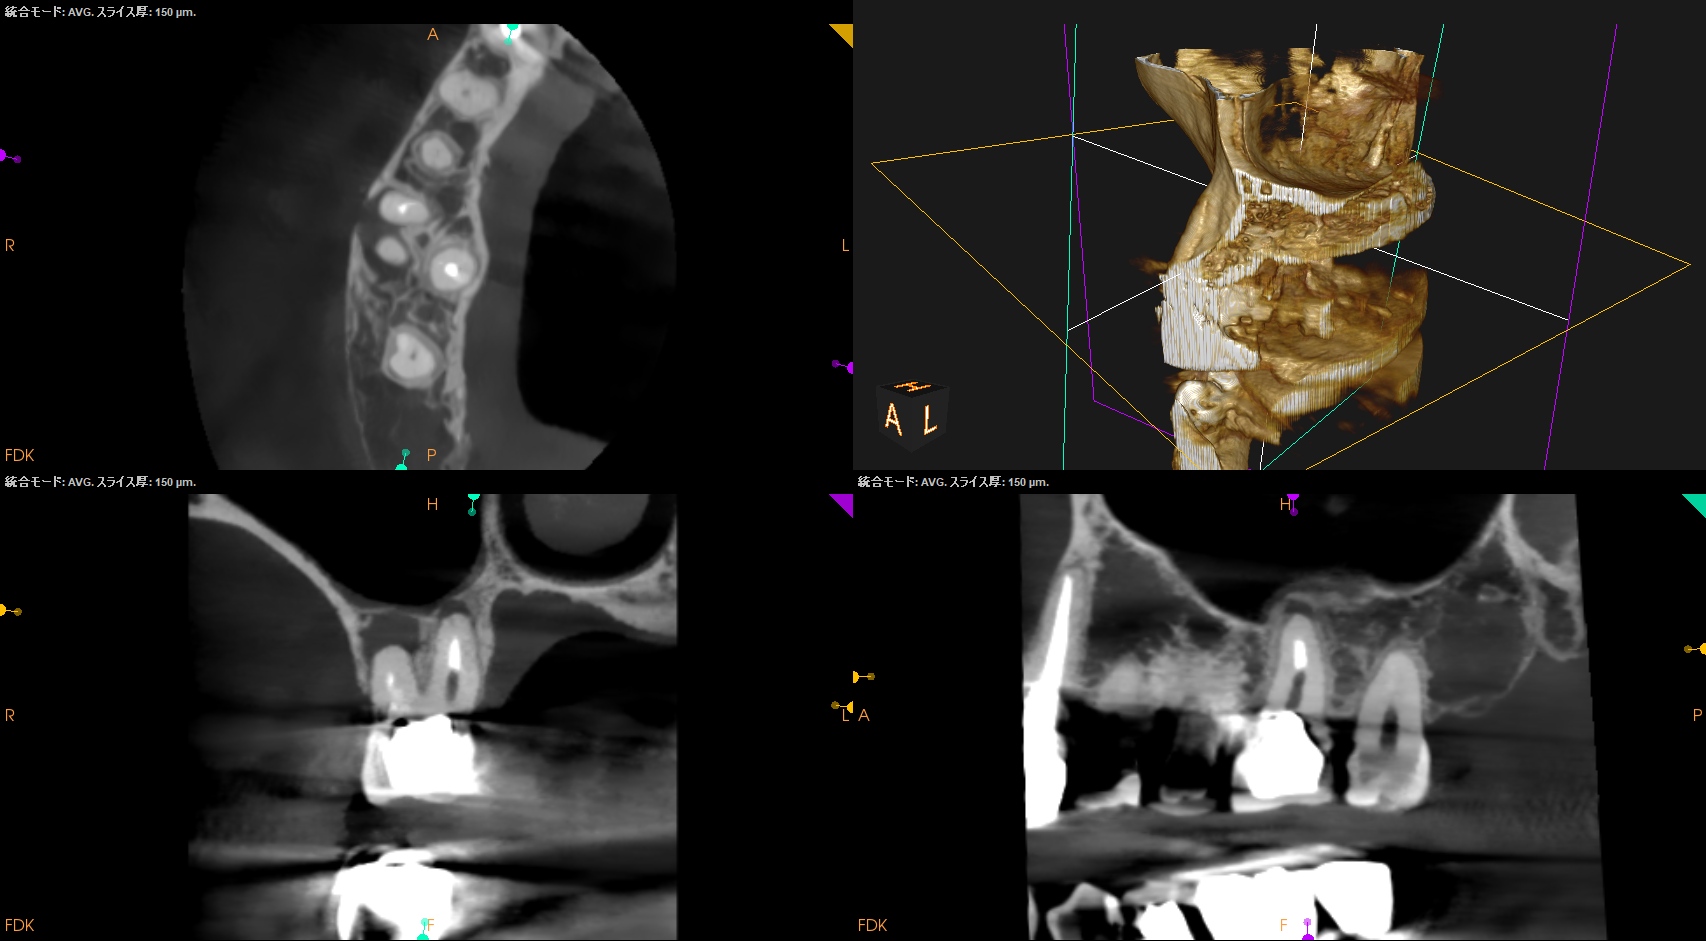

#3,14,16 Re-RCT 1yr recall(2025.10.20)

#3

MB

DB

P

#14

#16